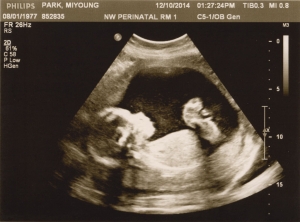

Last Ultrasound